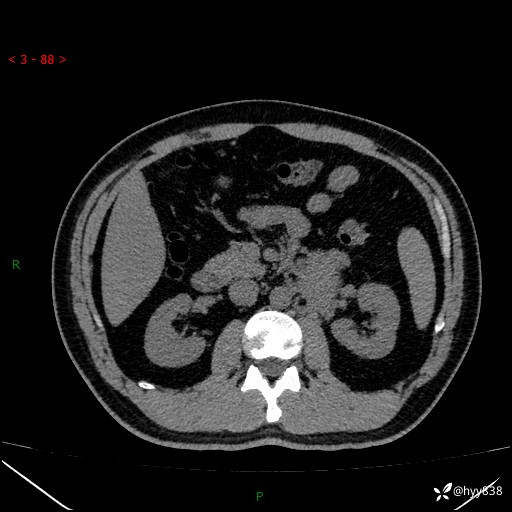

现病史:患者3月余前检查发现左侧腹膜后占位,大小约3.7*4.9cm,平素无腰疼,无肉眼血尿,无尿频尿急等不适,当时未特殊处理,在门诊复查CT提示左侧腹膜后占位,门诊拟“左侧腹膜后占位”收入院。 起病以来,患者精神佳,饮食、睡眠良好,大小便正常,体力体重无明显变化。

腹膜后CT平扫+增强